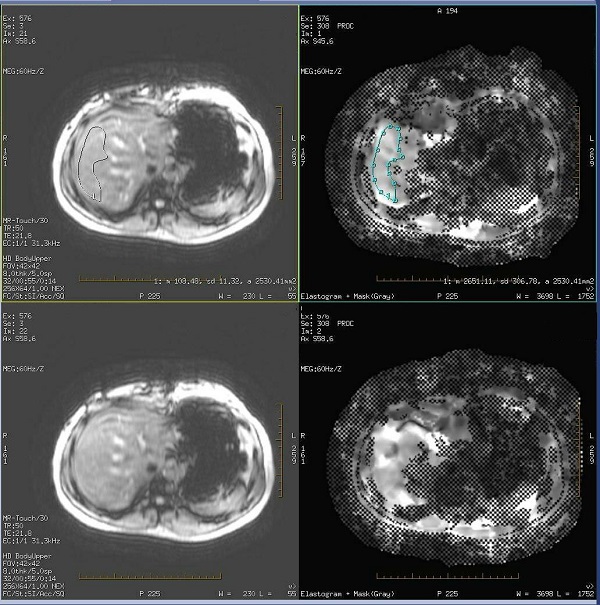

Figure 1. Measurement on source and Elastogram + Mask (Gray) series using Compare tool

MR-Touch: draw a ROI on an image

Use these steps to display an MR Touch series and to draw ROIs on the images. An alternative method is to display the MR-Touch series in READY View.

3. Click the Elastogram viewport to make it active so that you are drawing the ROI on the elastogram and masked image. You can draw the ROI on either image, but you may find it easier to first draw around the masked regions and then adjust the ROI around the vessels.

• The masked regions are hash-marked or checkerbox areas that indicate the wave propagation was not sufficient to confidently generate stiffness contrast. Including masked (checkerbox) areas in your ROI will skew the ROI statistics.

• Measurements should only be read on the Elastogram (Gray) images. Reading from the Elastogram+Mask images results in inaccurate values if any checkerbox masked region is included.